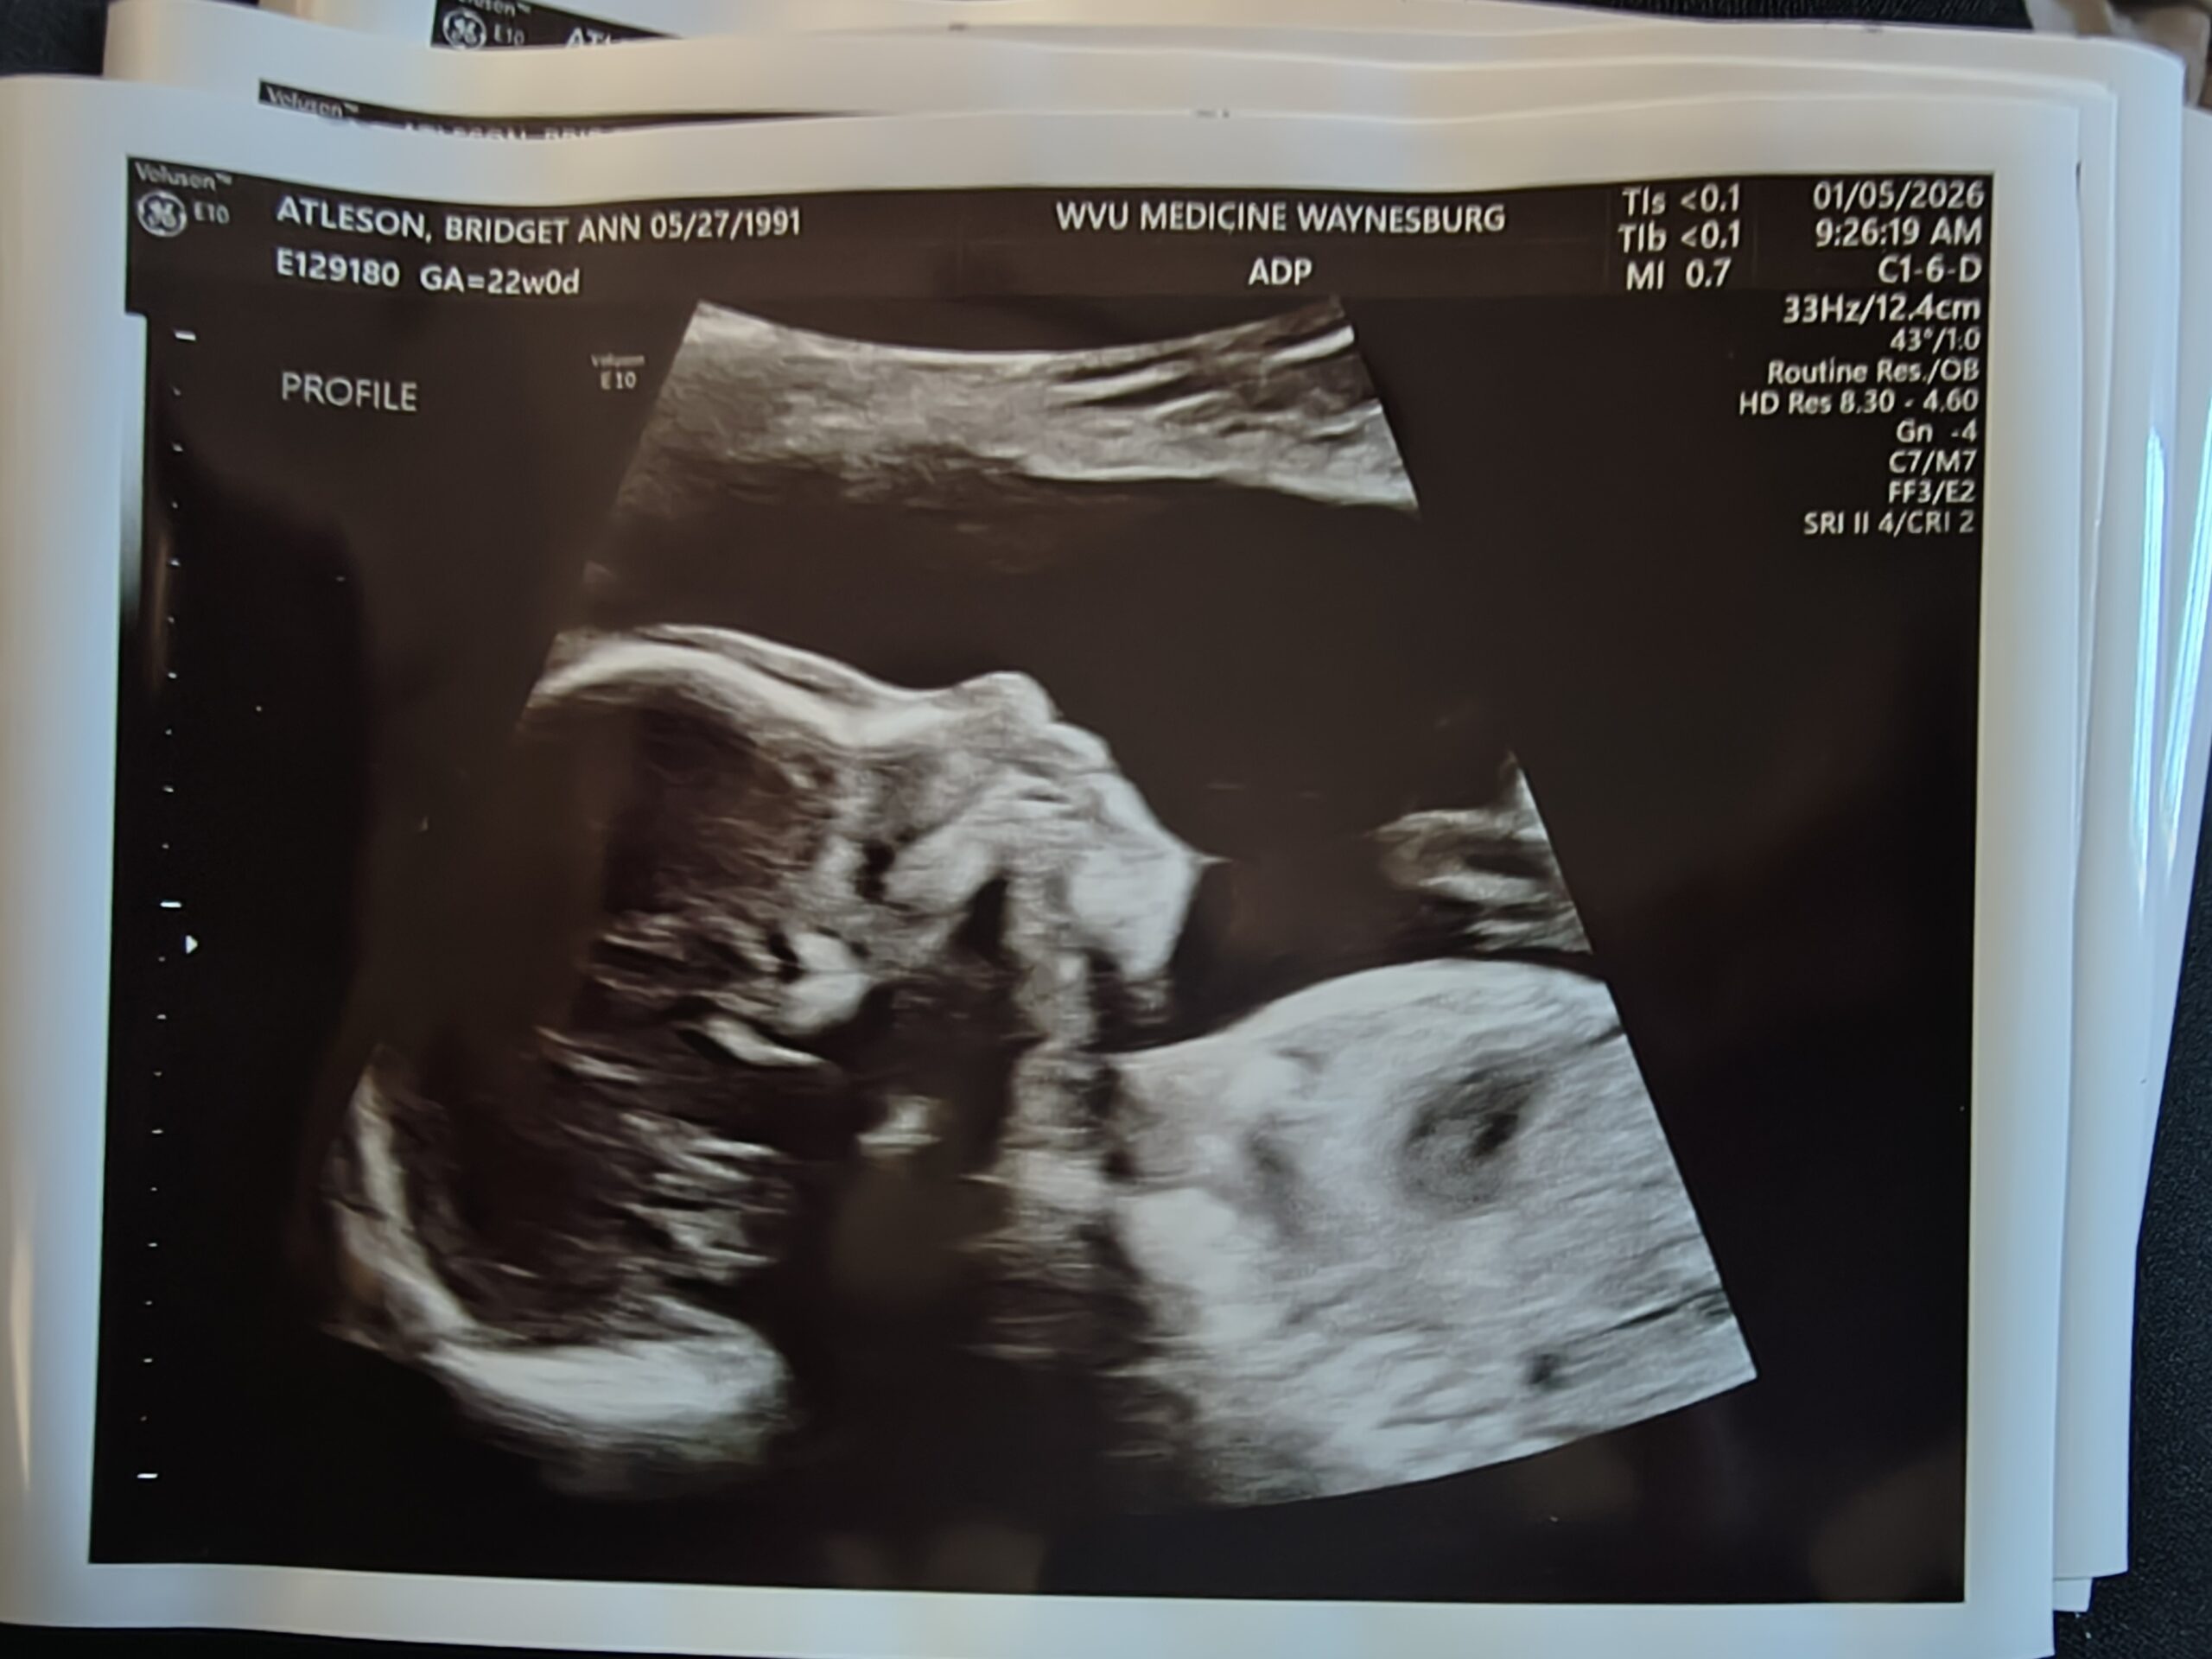

***Well, they were wrong — Two months after surgery we conceived our miracle baby, our first boy after having 4 beautiful girls.

We will welcome our baby in May of this year.